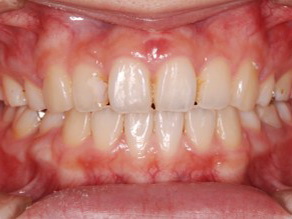

上顎前歯部のガタガタを気にして来院されました。上顎の左右第一小臼歯 (4番目の歯) を抜歯し、マルチブラケット装置で治療しました。治療期間は2年3か月でした。

初診時

終了時